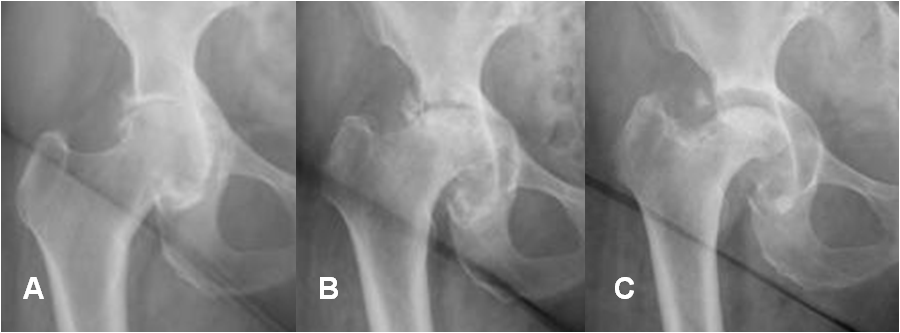

La enfermedad articular rápidamente progresiva, es una forma rara de osteoartritis, que compromete la cadera. Generalmente es unilateral, pero en algunos casos afecta ambas articulaciones.

Es común en mujeres jóvenes y se pueden encontrar cambios degenerativos de menor intensidad, en otras articulaciones.

En las radiografías seriadas, hay cambios progresivos con disminución del espacio articular y daño del hueso subcondral, de la cabeza femoral y la cavidad acetabular. (5).

(Fig 17 y 18).

Fig 17. Artropatía rápidamente progresiva.

A: Rx AP de cadera. Signos de osteoartrosis.

B: 3 meses y C: 6 meses después. Progresión de los cambios degenerativos, con deformidad la cabeza femoral y ensanchamiento de la cavidad acetabular.